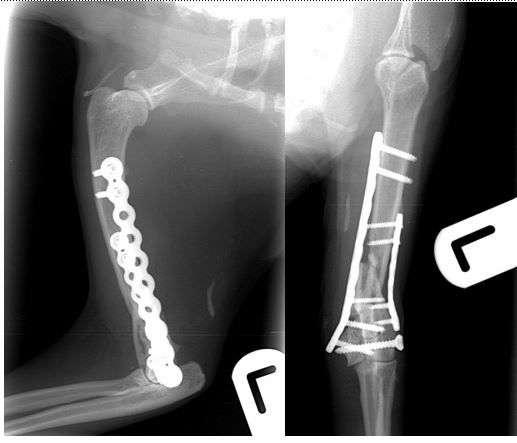

Preoperative radiographs showing a highly comminuted fracture of the left distal humerus.

Despite the catastrophic nature of the fracture it was possible to reconstruct the articular surface using a lag screw across the humeral condyle. The condyle was reattached to the shaft of the humerus using bilateral PAX locking plates. 12 weeks following surgery the cat had returned to normal activity and follow up radiographs showed complete healing of the fracture.

12-weeks post-operative radiographs